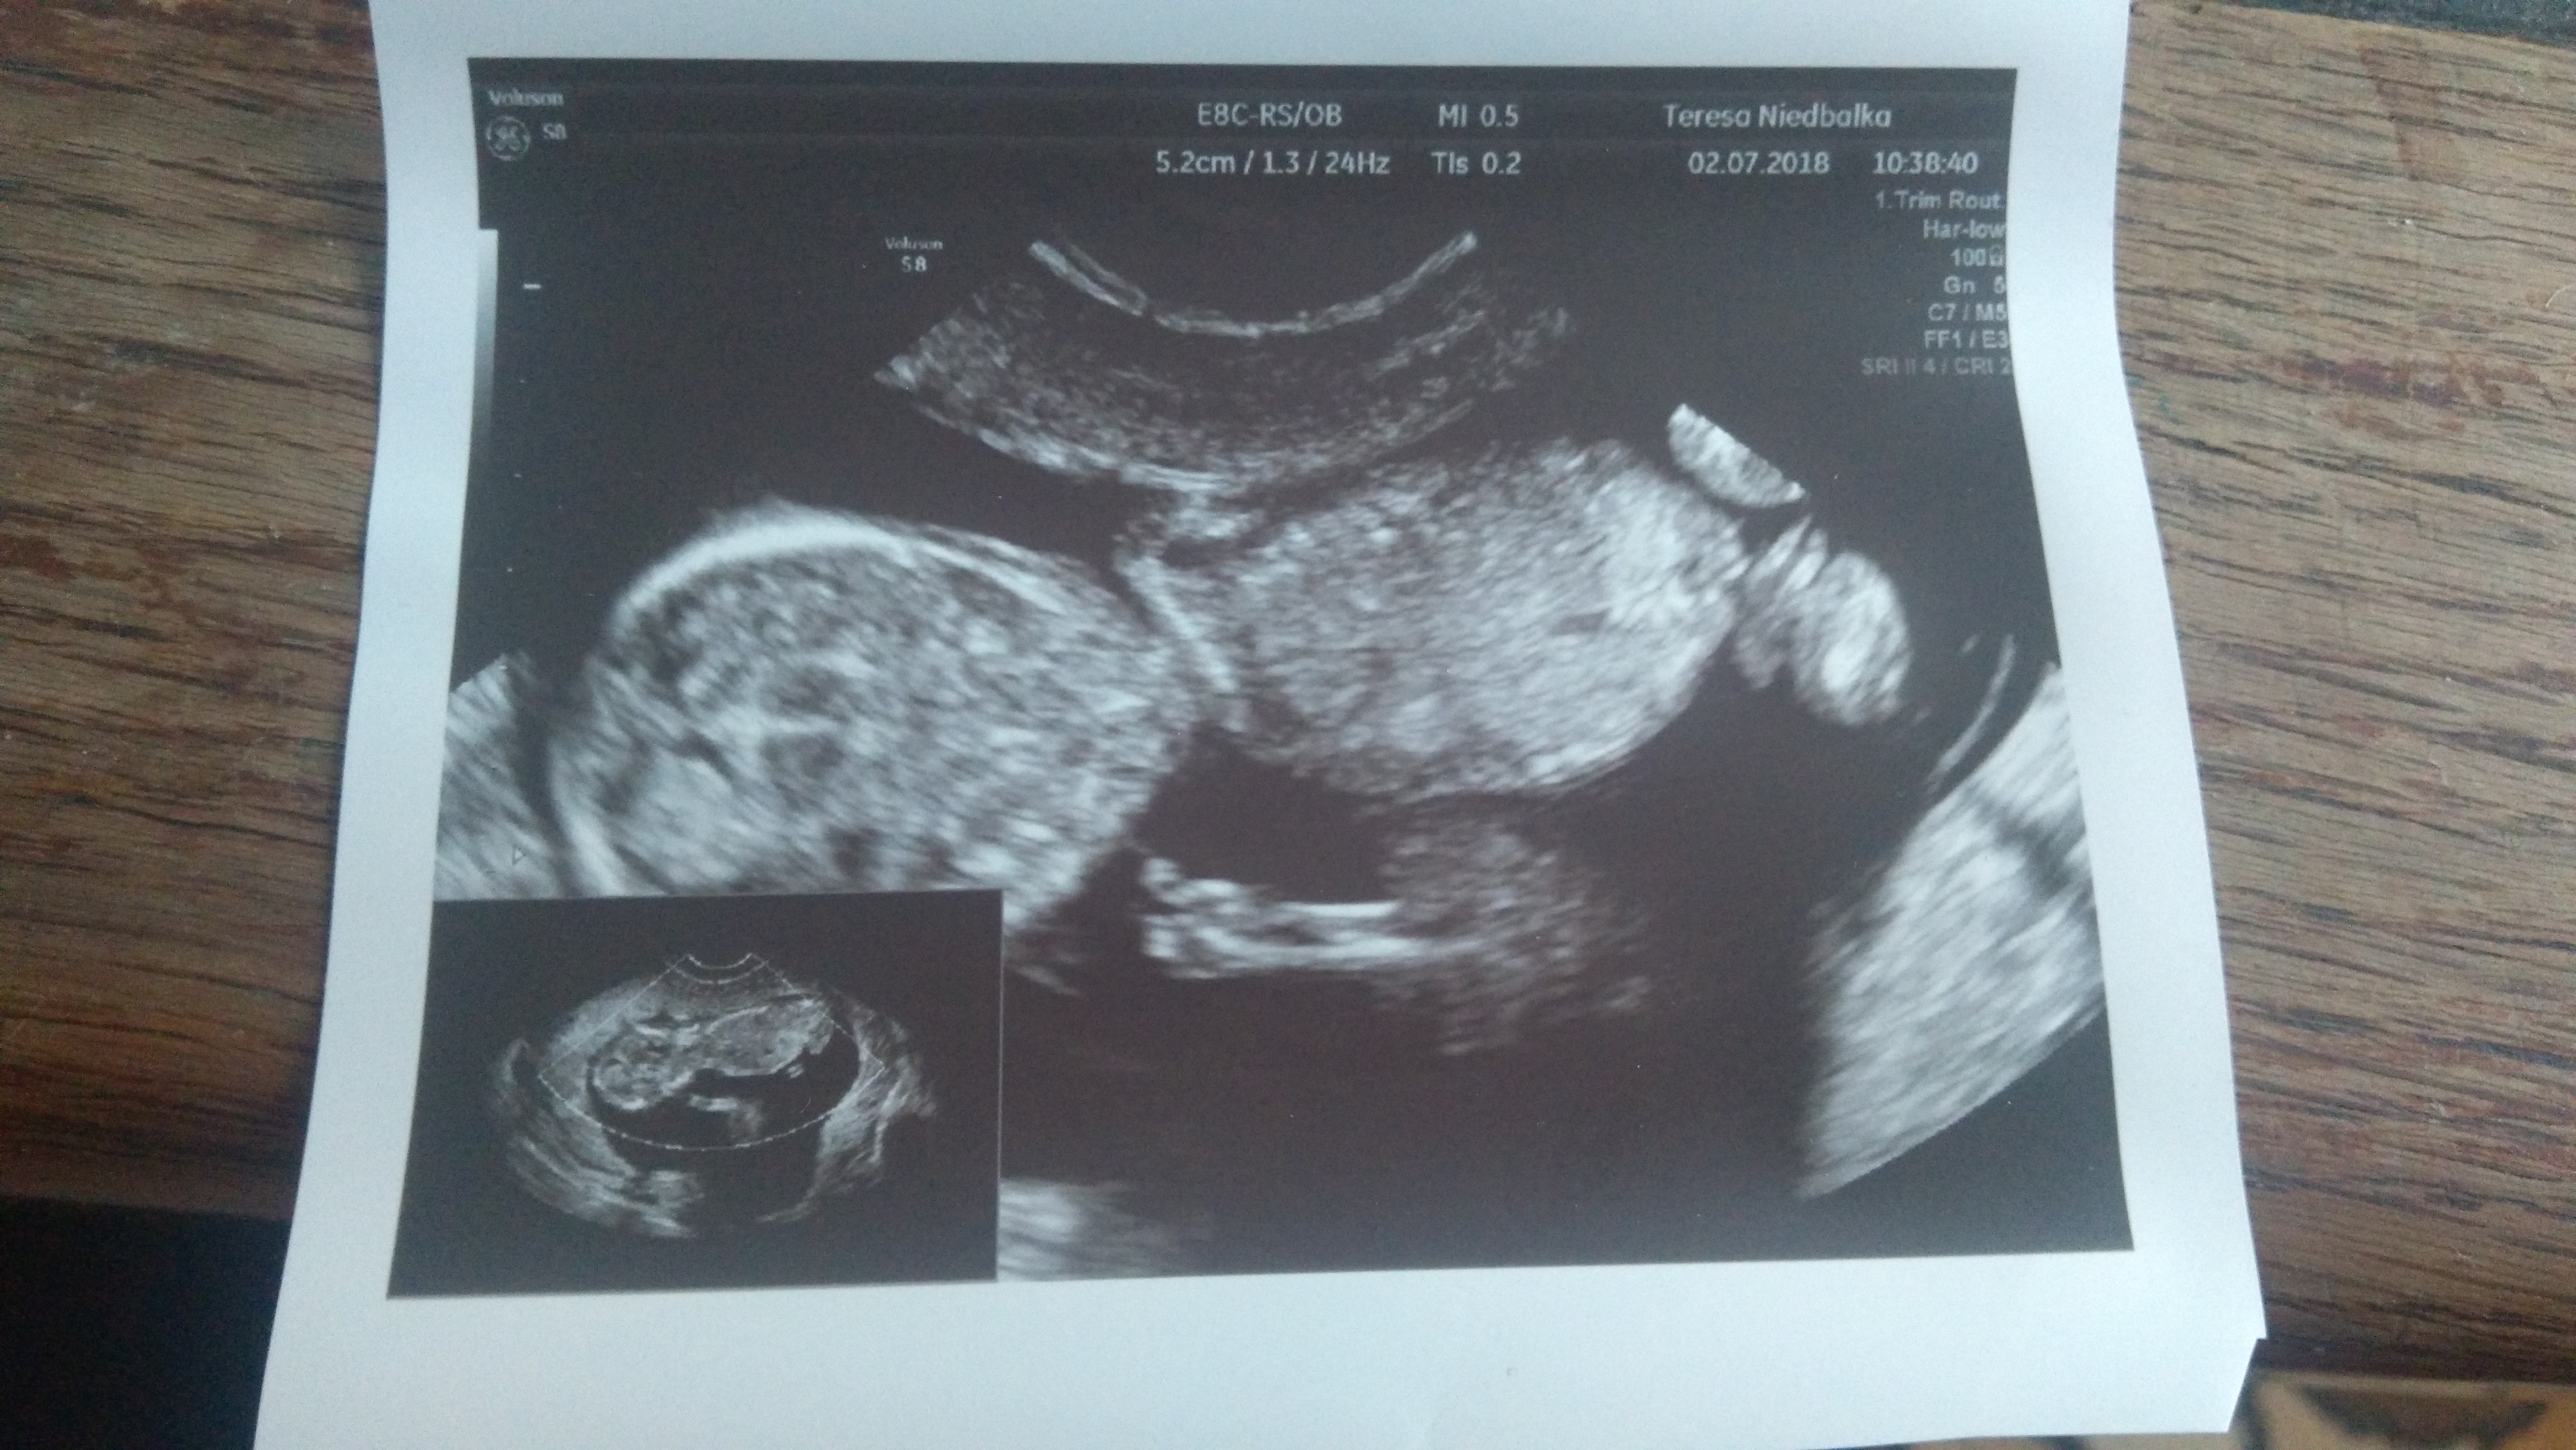

No więc.. Jest wszystko w porządku! Aaaa jestem najszcześliwa na świecie dziewczyny! Bibuś rośnie idealnie z OM i usg dzisiaj rownież wyszło 11+3. Ma 4.67cm [emoji7]

Termin dalej 19 styczeń. Widzieliśmy jak skacze, rusza rączkami, nożkami i ssie kciuk! Niesamowite! Serduszko puka 160/min [emoji7] Badania wszystkie ok. Szok bo TSH 0.66 [emoji50]

Prenatalne mamy 12.07 i 250zł. Test pappa zleca jak cos zobaczy nie tak w usg. Oczywiście schudłam troche ale nic nie mówił, wiec ok. Ciśnienie juz po wizycie bylo wiec bylo ok haha, przed to by skali brakło [emoji23]. Był ze mną maż i myślałam, że padnie z wrażenia jak zobaczył takiego bobaska na usg. To już nie "plama" tylko prawdziwy bobasek ! Zobacz załącznik 873204

A to moja dzidzia ma 12 tyg i 6 dni lubi się kręcić i wiercić do tego stopniaze nie dało się jej przez długi czas zmierzyć nawet bicia serduszka nie dala posłuchać haha wszystko z nią w porządku ma już 8 cm a jej kość biodrowa 1 cm